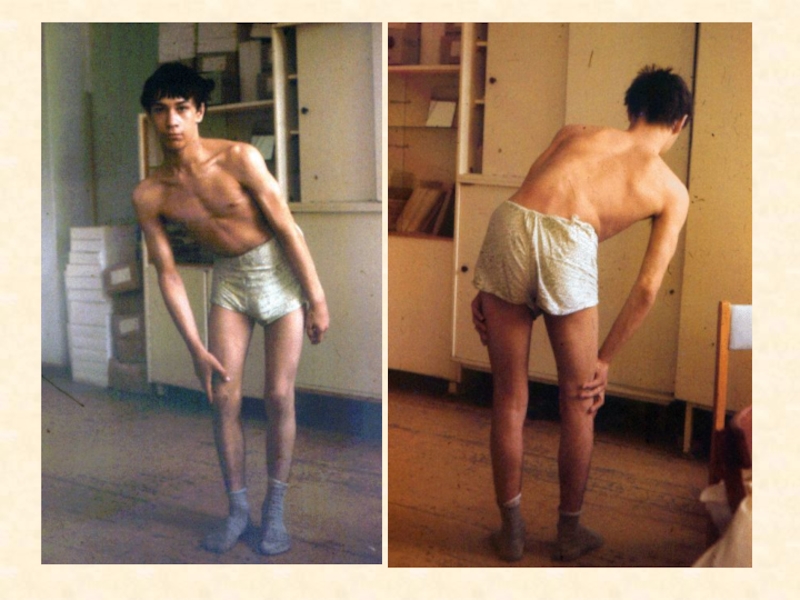

Визуальные материалы, связанные с болезнью Горхема-Стаута